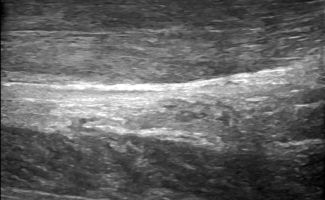

Foot Tendons

Foot Ultrasound allows the diagnosis of tendonitis, tenosynovitis, and rupture in the following tendons:

- Achilles Tendon

- Peroneal Tendons

- Flexor Tendons

- Extensor Tendons